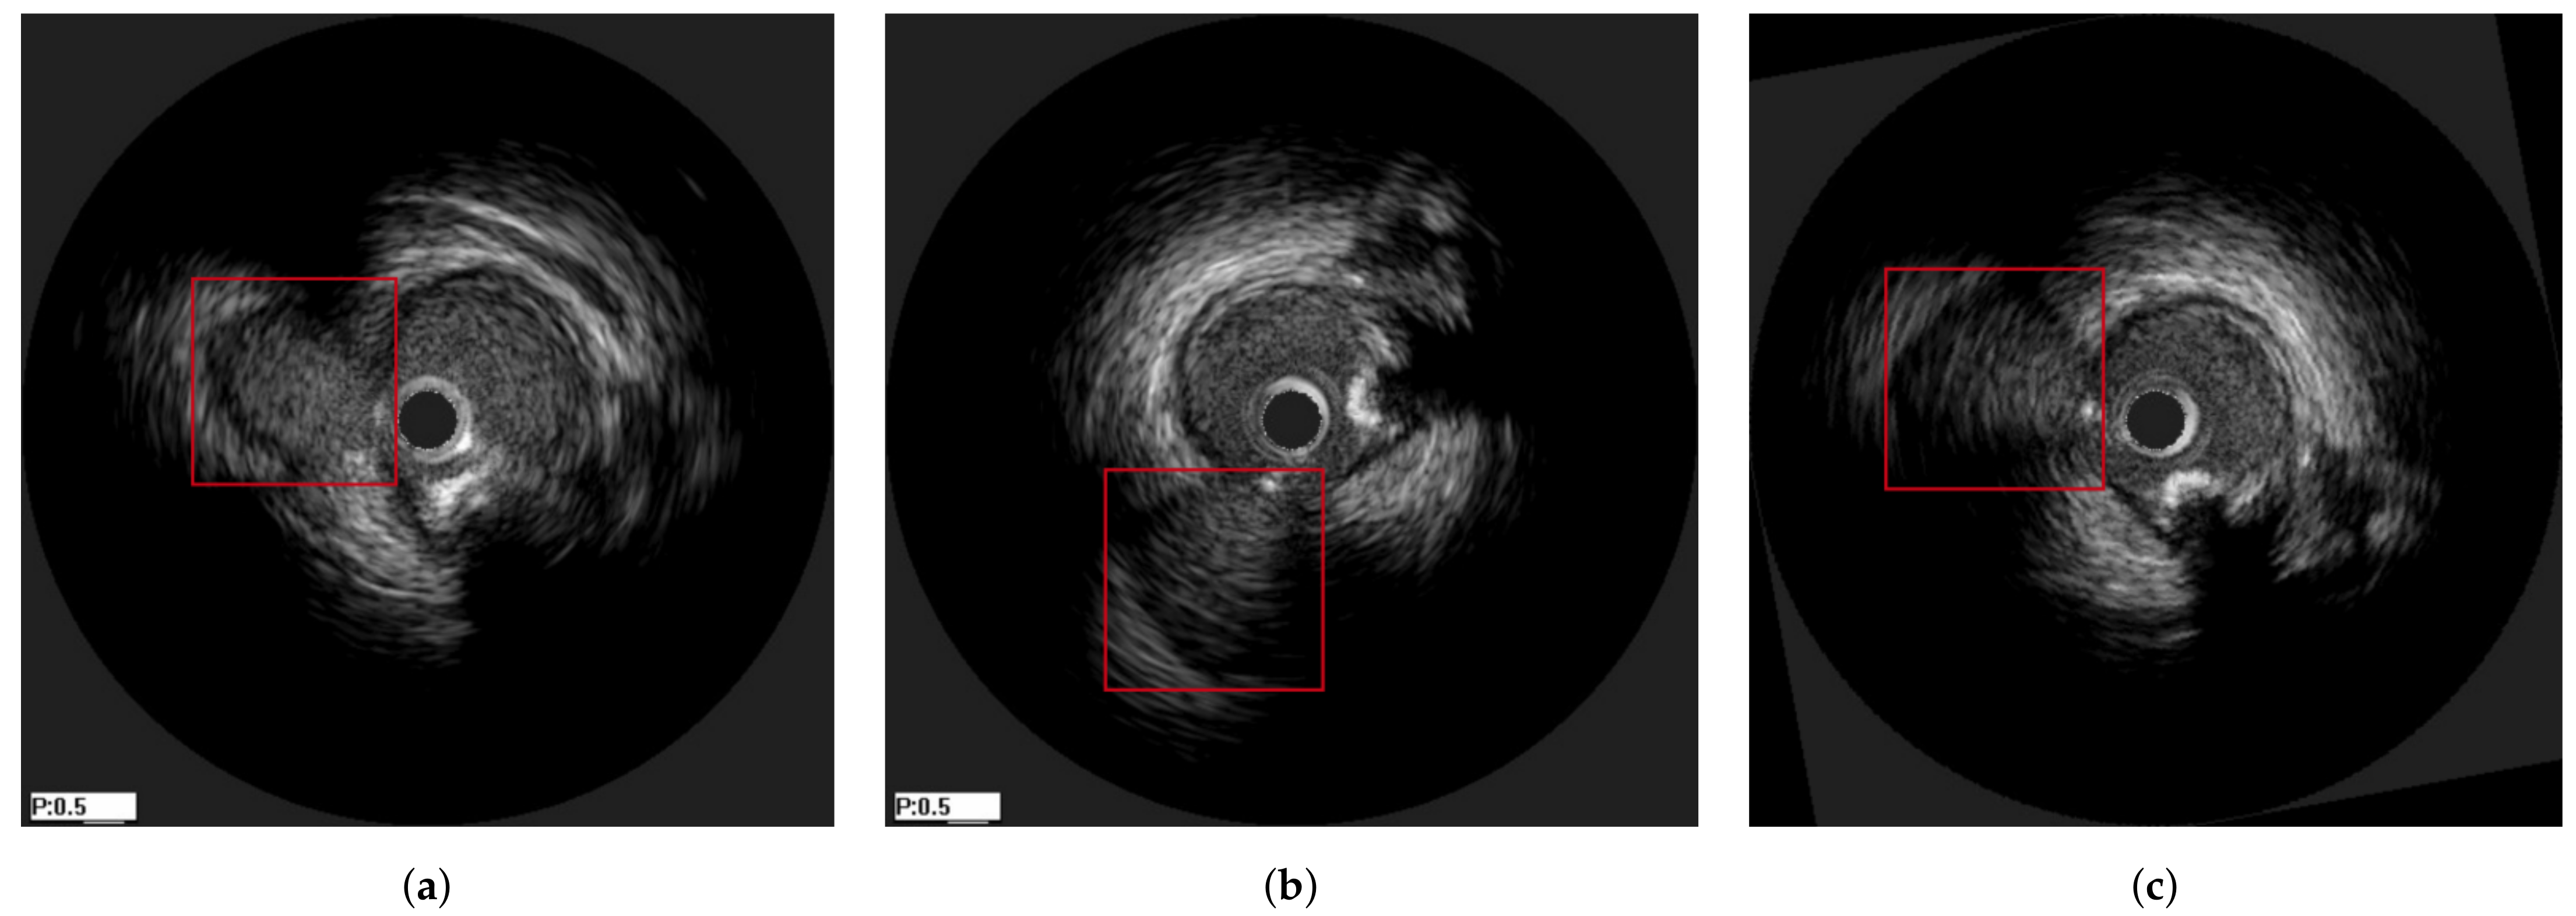

3.2. Longitudinal Registration

- Amplitude distortion, by adding random zero-mean Gaussian noise to the image.

- Partial overlapping, by discarding a subset of the pullback at its beginning and its ending. The length of the overlap was between 60–80% of the original size, randomly sampled based on the uniform distribution.

- Longitudinal distortion, by randomly repeating an image of the pullbacks to simulate the longitudinal oscillation of the probe. Each image in the pullback had a probability to be repeated, and the times of that repetition was randomly sampled between 1–4 based on the uniform distribution.

- Rigid distortion, by randomly translating and rotating an image to simulate the circumferential movement of the probe. The rotation range was , the translation range is pixels and both are sampled based on the uniform distribution.